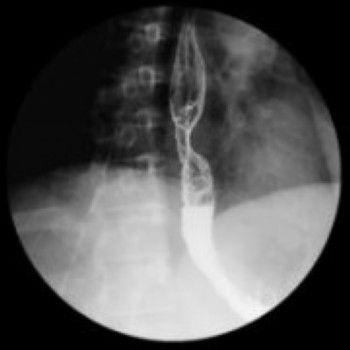

相关图片